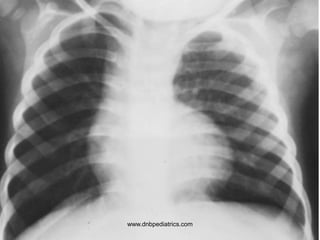

www.dnbpediatrics.com

Questions

1. Describe the X-ray appearance

2. Pathogenesis of the appearance

3. Possible Diagnosis

4. Which disorder is most commonly

associated with an elevated MCHC?

5. How is the corrected reticulocyte count

calculated?

1. Sunray appearance

2. Medullary widening

3. Chronic hemolytic anaemia

4. Hereditary spherocytosis

5. Corrected retic count

= reticulocyte % × (patient Hct/normal Hct)